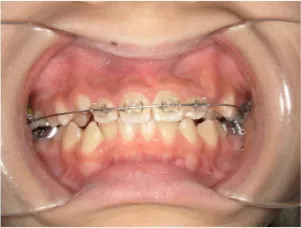

治療中④中1:治療中 マルチブラケット法へ移行

*マルチブラケット法移行前

*マルチブラケット法移行後